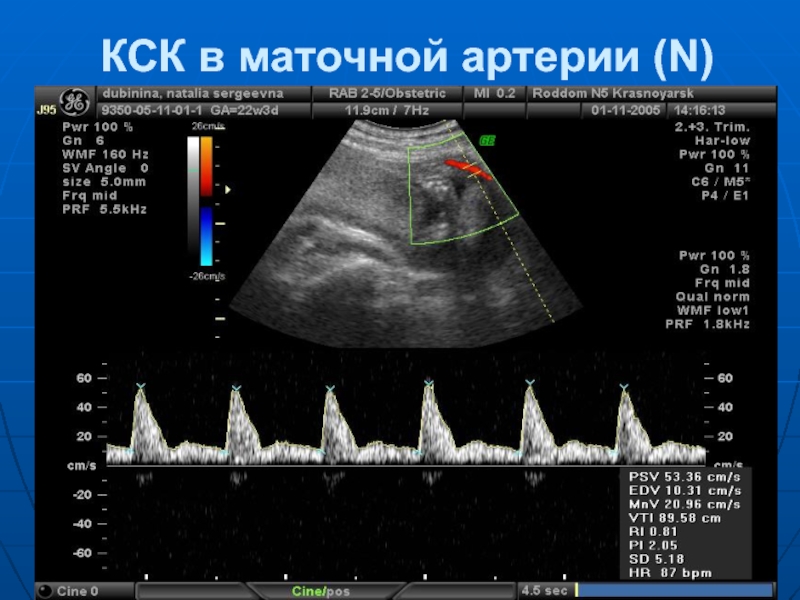

Слайд 35КСК в маточной артерии (N)

Слайд 30Допплерометрия (И.Х.Допплер - 1842 г.)

Наибольшую практическую

ценность имеет исследование кровотока в:

маточных артериях,

артериях пуповины

аорте плода.

Основные качественные показатели ДП:

СДО – систоло-диастолическое отношение (СДО = С / D)

IR – индекс резистентности

(IR = C – D / C )

PI – пульсационный индекс

(PI = C – D / Ccp.)

Слайд 33Изменения кровотока, регистрируемые только в маточных артериях - ранний диагностическим признаком

фетоплацентарной недостаточности.

А. Pagere et al. (1996), предлагает при нормальных показателях кровотока в маточных артериях и осложненном течении беременности родоразрешение производить в среднем в сроке 37,6 недель, а при нарушении кровотока в маточных артериях - в 31,1 недели беременности .